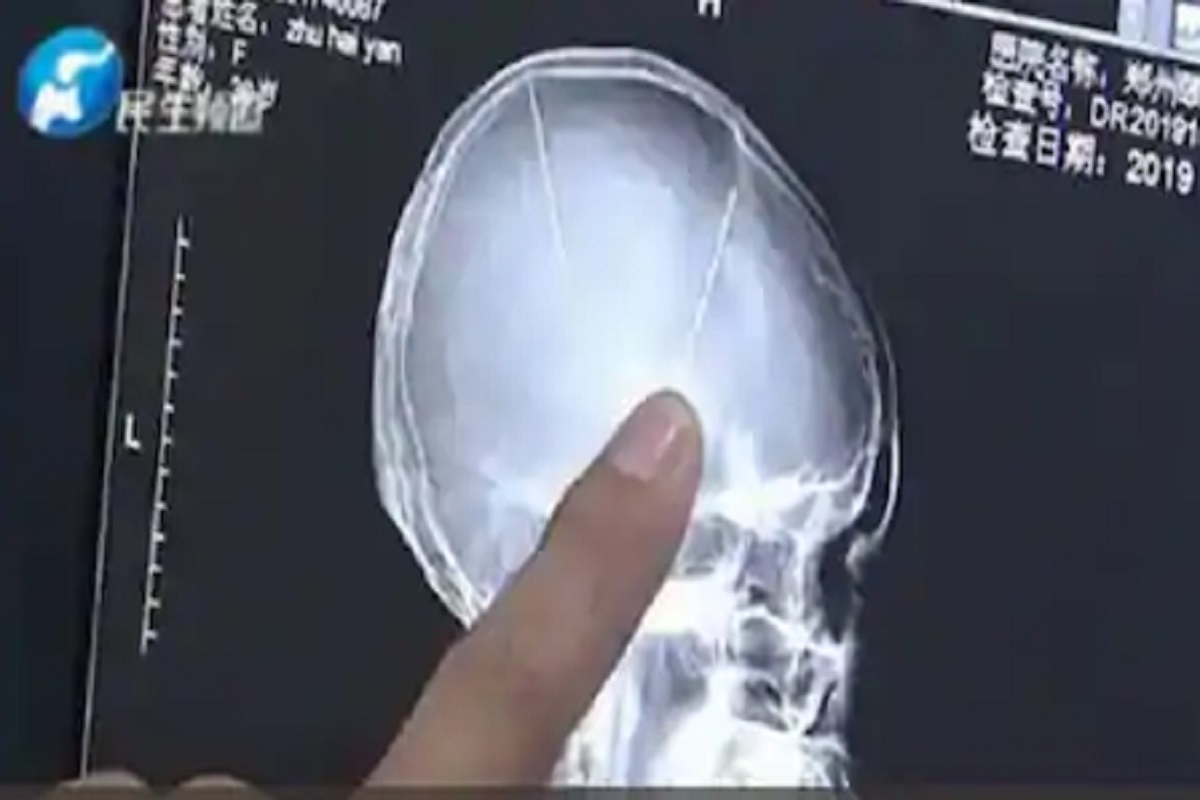

बीजिंग, 17 ऑक्टोबर : एखादा अपघात किंवा दुर्घटना झाल्यानंतर शरीरात एखादी धारदार वस्तू घुसण्याच्या घटना आजवर बऱ्याच घडल्यात. मात्र आता एक असं प्रकरण समोर आलं आहे, ज्यामध्ये किरकोळ अपघात झाला, डोक्याला कोणतीही दुखापत झाली नाही. मात्र त्या व्यक्तीच्या मेंदूत टोकदार वस्तू घुसलेल्या दिसल्या. हे पाहून डॉक्टरही हैराण झाले. ही घटना आहे चीनमधील (china). जेंगझाऊनमधील 29 वर्षीय महिलेचा (Chinese Woman) छोटासा कार अपघात (Car Accident) झाला. तिला फारशी दुखापत झाली नव्हती डोक्याला आतून मार लागला नाही ना हे तपासण्यासाठी डॉक्टरांनी तिला डोक्याचा सीटी स्कॅन(CT Scan) करायला सांगितलं. तिच्या सीटी स्कॅन रिपोर्टमध्ये अपघातामुळे तिला कोणतीही दुखापत झाली नाही हे स्पष्ट झालं. मात्र तिच्या मेंदूत काहीतरी विचित्र वस्तू असल्याचं दिसलं. ही वस्तू म्हणजे टोकदार सुई (Needles) होती. झू नावाच्या या महिलेच्या मेंदूत अशी एक नाही तर दोन सुया होत्या. या सुयांची लांबी 5 सेमी आणि व्यास 4.9 मिमी होता. या दोन्ही सुया तिच्या मेंदूत खोलवर रुतल्या होत्या. विशेष म्हणजे या सुयांचा कार अपघाताशी संबंध नव्हता. म्हणजे या सुया कार अपघातामुळे महिलेच्या मेंदूत गेल्या नव्हत्या. कारण तशा काही जखमा या महिलेच्या डोक्यावर नव्हत्या. याशिवाय महिलेनं आपल्याला कधी डोक्याला गंभीर दुखापत झाली असावी याची माहितीही नव्हती. हे वाचा - तरुणीच्या डोळ्यातून खरंच वाहू लागले ‘खून के आंसू’; पाहून डॉक्टरही झाले हैराण त्यामुळे कदाचित या महिलेनं या सुया लहान असताना डोक्यात मुद्दामहून घुसवल्या असतील, असा अंदाज डॉक्टरांनी व्यक्त केला आहे. कारण प्रौढ व्यक्तीच्या डोक्यात इतक्या मोठ्या सुया रुतणं शक्यच नाही, असं डॉक्टर म्हणाले. दरम्यान चीन वेबसाईट सोहूच्या रिपोर्टनुसार, महिलेने याबाबत पोलिसात तक्रार केली आहे. या सुया तिच्या मेंदूत कुणी दुसऱ्या व्यक्तीने रुतवल्या असाव्यात असा संशय तिला आहे. मात्र तिला लगेच कुणाचं नाव घ्यायचं नाही.